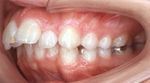

上顎前突150.jpg

→上顎前突 (出っ歯)